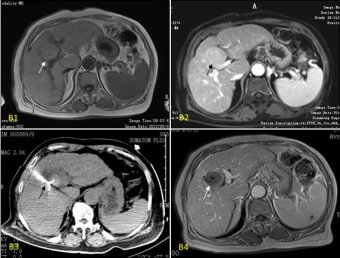

之所以能對肝癌進行局部治療,這首先得益于肝臟理想的位置。肝臟位于右上腹部,大頭朝外,右肋部的一大片皮膚與肝臟只是“一墻之隔”。這樣的位置,在運用射頻消融微創(chuàng)技術(shù)治療肝癌時醫(yī)生通過穿刺的方式能夠很容易地進到肝臟,在CT或B超的引導(dǎo)下找到癌灶部位實現(xiàn)靶向性消融。因此,光有理想的位置是不夠的,兩項里程碑式的診療技術(shù)孕育了肝癌局部治療的概念,那就是早期診斷技術(shù)的出現(xiàn)(如肝臟CT、核磁共振)和超聲技術(shù)的應(yīng)用。前者讓人們有能力發(fā)現(xiàn)小肝癌,后者能夠幫助醫(yī)生對肝癌病灶進行較準確的定位,就如同醫(yī)生長了一雙透視眼。

一般認為外科切除是肝癌的根治方法,但手術(shù)切除率一直很低。對不能手術(shù)的病人常采用TACE及PEI進行治療,但效果常不盡如人意,原因在于其常需要多次治療從而導(dǎo)致肝功能損傷加重,對于少血供的病灶TACE治療效果不佳。射頻消融術(shù)(radio-frequency ablation,RFA)治療肝臟腫瘤于1995年由意大利的Rossi率先應(yīng)用于臨床,是當(dāng)今最新的肝腫瘤導(dǎo)向治療方法之一,許多臨床資料證明:對于治療肝癌,射頻消融術(shù)是一種有效的安全的治療方法。其基本原理是:進入組織的電極發(fā)出射頻波,使組織內(nèi)的分子相互撞擊摩擦,產(chǎn)生熱能,使組織細胞凝固壞死,同時,腫瘤組織對熱的耐受遠低于正常肝組織,所以腫瘤組織壞死較完全,肝組織得到相應(yīng)保護。這種手術(shù)可以達到使患者長期無腫瘤生存,實現(xiàn)正常工作和生活的目的,并且由于射頻是微創(chuàng)治療,可隨腫瘤反復(fù)發(fā)作進行再治療。濰坊市市立醫(yī)院普外科自2000年由國外引入開展運用于治療肝臟惡性腫瘤,經(jīng)過10余年的實踐證實,射頻消融為不能手術(shù)切除的臨床治療困難的肝腫瘤患者提供了很有效的局部治療。》》不清楚該療法是否適用于自己?點擊咨詢在線腫瘤專家

臨床證明對5厘米以下肝癌患者采用射頻消融治療,患者1年生存率為100%,3年生存率達到了95.1%;對治療5厘米以上射頻消融技術(shù)可消融腫瘤最大直徑為16厘米,這類的患者1年生存率為96.9%。3年生存率達到了85.1%。射頻消融治療肝癌不僅有生存率高的特點,還能實現(xiàn)預(yù)測控制治療范圍,監(jiān)測熱場的溫度,被譽21世紀治療肝癌最具應(yīng)用前景的治療手段。